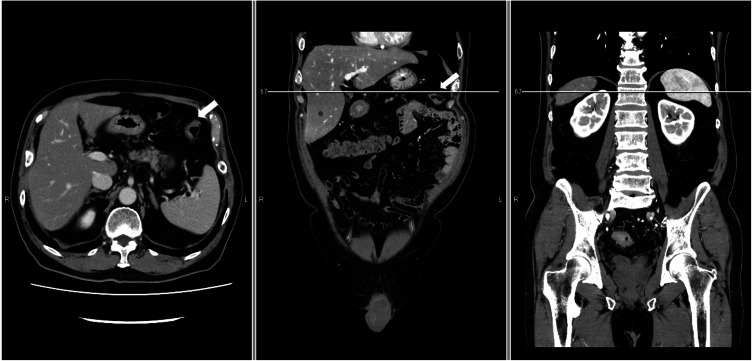

Purpose: In surgery for rectal cancer, splenic flexure mobilization is sometimes necessary to ensure a tension-free colorectal anastomosis with adequate blood supply. Splenic flexure mobilization is regarded as a challenging and risky maneuver, but there are no clear indicators of its difficulty in rectal cancer surgery. This study evaluated the impact of clinical and anatomical factors, including splenic flexure height measured qualitatively on the basis of vertebral level using computed tomography, on the difficulty of splenic flexure mobilization during rectal cancer surgery.

Methods: The enrolled patients underwent robotic splenic flexure mobilization during rectal surgery for primary rectal cancer at Shizuoka Cancer Center in Japan between December 2011 and March 2022. All patients were scheduled to undergo splenic flexure mobilization preoperatively, and all procedures were carried out following a standardized approach. Linear regression analysis was conducted to determine the clinical and anatomical factors significantly influencing the operative time of the abdominal phase, which is defined as the duration from lymph node dissection around the inferior mesenteric artery to the mobilization of the sigmoid and descending colon, including the splenic flexure.

Results: The median operative time for the abdominal phase was 88 min (range, 39-179 min). Univariate analysis revealed that the following variables were significantly correlated with a prolonged abdominal phase: higher body mass index, larger visceral fat area, and higher splenic flexure. In a multiple linear regression analysis, only higher splenic flexure remained significantly associated with a longer abdominal phase (p < 0.01).

Conclusions: Splenic flexure height measured on the basis of vertebral level using computed tomography may be useful for predicting the difficulty of robotic splenic flexure mobilization in surgery for rectal cancer.